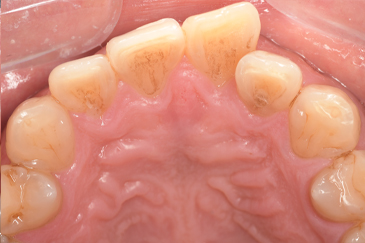

CASE 10

Before①

After①

Before②

After②

基本情報

| 年齢・性別 | 38歳・男性 |

| 主訴 | 下顎 歯石除去したい |

| 治療内容 | スケーリング |

| 治療期間 | 30分 |

| 治療費 | 約1,500円(保険診療) |

| リスク・副作用 | 知覚過敏、歯肉退縮 |

| 治療方針 | 歯肉縁上歯石を除去してから歯肉縁下歯石を除去します。ご自身でのプラークコントロールができるようになったら定期検診に移行します。 |

| 担当者所見 | 半年ぶりの歯科医院の受診。歯石が付きやすいためセルフケアの重要性をお伝えして、定期的にクリーニングを行います。出血率が高く炎症が強いため、今後はセルフケアを強化して歯周病治療を行います。 |